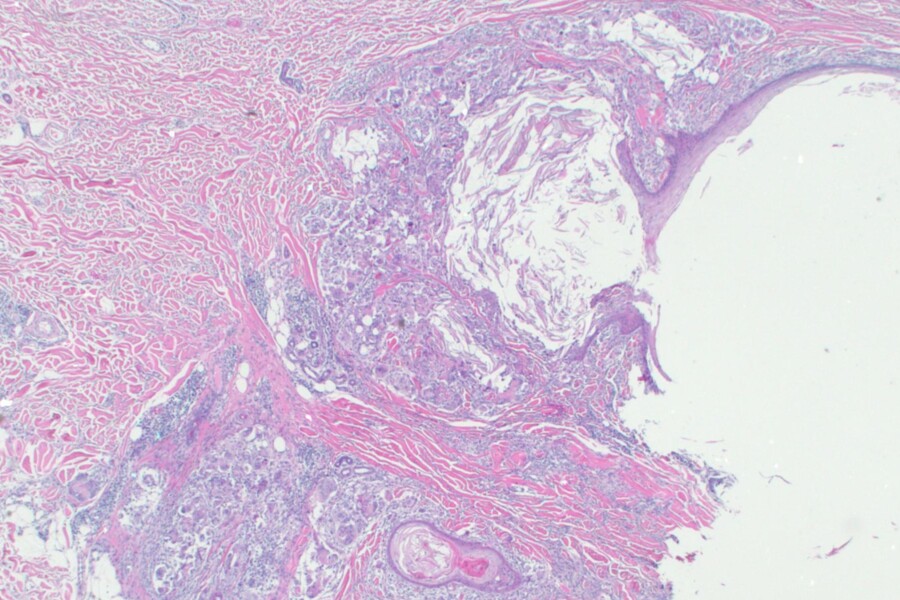

Cysty jsou dutiny vyplněné tekutinou nebo hutnou hmotou a mohou se tvořit kdekoliv v těle. Ve většině případů se tkáň začne cysticky měnit a vytvoří cystu bez jakékoliv zjevné příčiny. Platí to pro naprostou většinu cyst. Příznaky cysty závisejí na jejím umístění a typu. Pokud se cysta nachází pod kůží, většinou se projeví jako zduření nebo hrbol, u vaječníků může cysta vyvolat pocit napětí v břiše.

Cysta je jakákoliv abnormální dutina obsahující tekutinu nebo i hutnou hmotu. Tyto dutiny se mohou vytvořit v jakémkoli orgánu nebo tkáni lidského těla a mohou mít různou velikost - od zcela maličkých až po rozsáhlé útvary obsahující i litry tekutiny.

Většina cyst je benigní (nezhoubná); mohou se zvětšovat, ale nešíří se nikam ani nenapadají okolní tkáň. Některé jsou maligní (zhoubné) a mohou se šířit a napadat jiné tkáně.

Dermoidní cysta se vytvoří proto, že některé kožní buňky jsou uvězněny během vývoje v hloubce kůže a nevycestují normálně na povrch. V podkoží vytvářejí tekutinu a výsledkem je cystický útvar.